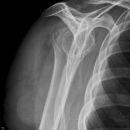

Subcapitale Fraktur und Tuberculum majus